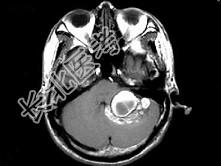

- 单项选择题男,45岁, 反复呕吐近1个月,加重5天, 根据所提供图像,最可能的诊断是 ( )

A、海绵状血管瘤

B、静脉血管畸形

C、脑出血

D、动静脉畸形

E、小脑胶质瘤并出血